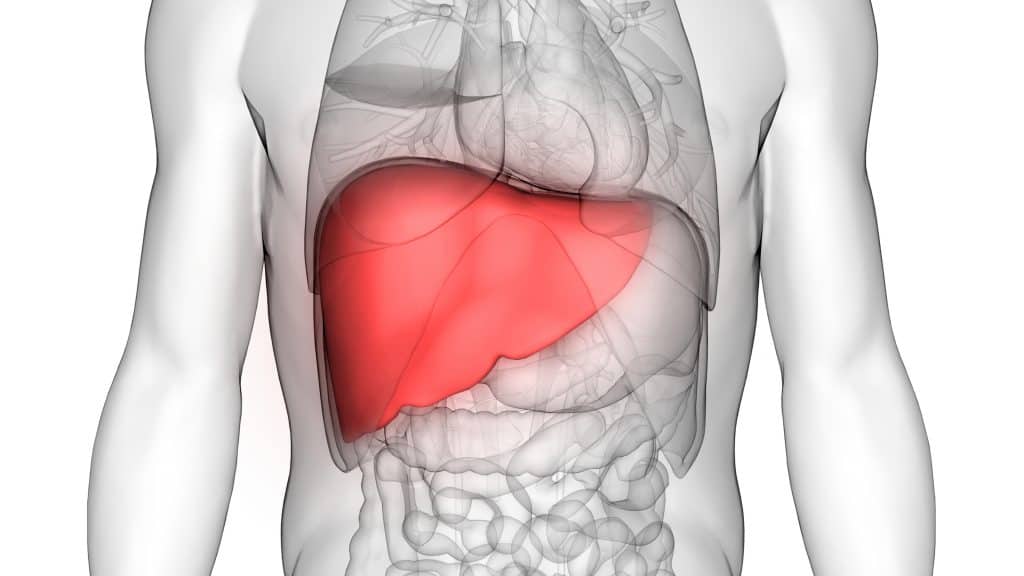

Jetra je naš najveći unutrašnji organ i ona je zaslužna za prerađivanje svake tvari koje smo unijeli u naš organizam. Često zaboravimo na važnost jetre, što može dovesti do raznih bolesti koje su uzrokovane nezdravim načinom života. Gdje se nalazi jetra u tijelu? Jetra je svoj organ, što znači da je ona neparni organ i nalazi se točno ispod desnog rebrenog kuka u trbušnoj šupljini odmah ispod dijafragme. Pošto je riječ o našem najvećem organu, u odraslih ljudi ona teži oko 1. 5 kilograma. Kako izgleda jetra? Jetra je po izgledu crvenosmeđi organ koji je mekan i sastoji se od dva različite veličine režnja, desni je tako veći od lijevog. S donje strane svake jetre, između njenih samih režnjeva se nalazi hilus ili isto tako zvana Porta jetre. Kroz navedeni hilus ili portu jetre u svaku jetru ulaze određene krvne žile, kao i živci i žučni kanali. Na donjoj strani desnog jetrenog režnja nalazi i žučni mjehur koji također ima važnu funkciju u našem organizmu. Važno je naglasiti da je jetra obavijena vezivnom ovojnicom koja prilikom rastezanja uzrokuje bol u jetri. Jetra također ima dvostruku opskrbu krvlju, što znači da kroz nju prođe oko 1. 5 litara krvi u svakoj minuti. Sada kada znamo gdje se nalazi jetra, važno je da opišemo njene funkcije u našem tijelu.

Jetra je svakako kompleksni organ u našem tijelu, no ona je isto tako moćno oružje u zaštiti našeg organizma protiv svim opasnih i štetnih stvari. Jetra se ponaša kao filter u našem organizmu. Koje su najvažnije funkcije jetre? Ona refulira šećer u našoj krvi, stvara kolesterol, stvara protutijela i transportne proteine, eliminira bilirubin iz organizma i amonijak, stvara žuč za probavu masti u našim tijelima, skladišti vitamine A, D, E, B12, Željezo, razgrađuje inzulin, radi detoksikaciju organizma kada su u pitanju lijekovi i toksini, razgrađuje alkohol. Funkcija jetre je da nas održava zdravima i zaštićenima. Sada kada znamo gdje se nalazi jetra i koje su njene glavne funkcije u našem tijelu sljedeća stvar koju moramo znati je kako održati jetru zdravom? Jetra ima najglavniju zadaću u našem cijelome tijelu, a to je metabolizirati svaku tvar koju smo tijekom svog života unijeli u sebe. Preveliki unos štetnih stvari, nezdrava prehrana, alkohol i lijekovi kroz godine sve teže padaju na jetru i oštećuju njenu funkciju. Poremećena funkcija naše jetre odražava se na naše cjelokupno zdravlje, a njenim usporenim radom dolazi do stanja kroničnog trovanja. Kako bi izbjegli njeno oštećenje i održali je zdravom postoje određene stvari koje nam mogu pomoći. Gdje se nalazi jetra? Pošto se jetra nalazi u našoj trbušnoj šupljini, ponekad se bol jetre može manifestirati i u desnom gornjem djelu trbuha.

Jetra je najveći organ u našem tijelu. Ona je izuzetno važna za detoksikacijski proces i filtriranje svim toksina iz naše krvi. Gdje se nalazi jetra? Ona se nalazi ispod našeg desnog rebrenog luka u trbušnoj šupljini ispod dijafragme. Jetra pomaže u našoj probavi i pohranjuje energiju. Pošto je vrlo osjetljiva na toksine iz lijekova važno ju je održavati zdravom, osobito ako redovito konzumirate lijekove radi određene bolesti. Kako održavati jetru zdravom? Zdrava prehrana je svakako prvi korak. Jedite hranu koja sadržava manje količine trans masti i fruktoze, jedite manje prerađene hrane i okrenute se svježim namirnicama. Ako ste pušač svakako je poželjno da prestanete pušiti, ili barem smanjite. Alkohol je dobro poznat neprijatelj jetre, i njegova umjerena konzumacija je poželjna. Mora postajati i određeni oprez pri uzimanju lijekova. Ako iz nekog razloga jedno vrijeme morate koristiti neku prepisanu terapiju, tada bi bilo dobro da uzimate i nešto za očuvanje jetre. Danas u ljekarnama tako možete naći brojne prirodne lijekove koji su osmišljeni za očuvanje jetre. Gdje se nalazi jetra je važno pitanje kako bi znali reagirati u slučaju da osjetimo bol, no kao što znamo ona je „tihi organ“ i upravo zato je važno voditi brigu o njenom funkcioniranju koje i nas održava zdravima